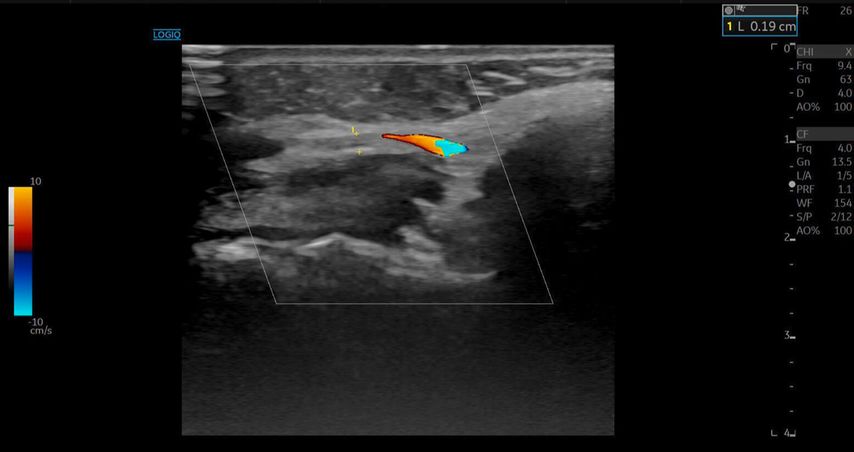

Die A. facialis imponierte beim Austritt im Bereich des Musculus masseter (oberhalb der Kieferlinie) vasospastisch mit einem maximalen Durchmesser von 1mm. Die abgeleitete systolische Spitzengeschwindigkeit betrug trotz der bestehenden Ischämie 20cm/s, ohne enddiastolische Komponente, was auf eine weitere periphere Vasokonstriktion hindeutete (Abb. 2 und 3).